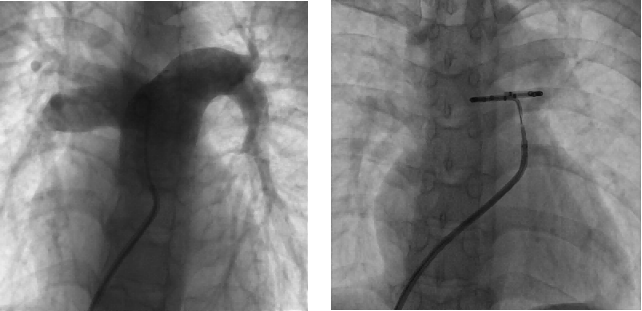

手术中,团队根据 DSA 肺动脉造影,结合术前肺动脉 CTA 影像,选择最佳型号的 PADN 消融导管,确定消融靶点后,精准消融。

团队通过科学诊断、充分评估,成功应用全球首创、中国原创的 PADN 环形肺动脉射频消融导管,对肺动脉神经节消融靶点进行「点对点」精准消融,手术顺利。PADN 术后 RHC 血流动力学参数较术前明显改善,其中,平均肺动脉压即刻下降 16%,肺毛细血管楔压即刻下降 25%。术中及术后患者无不适,生命体征平稳,安返病房,此次手术圆满成功。